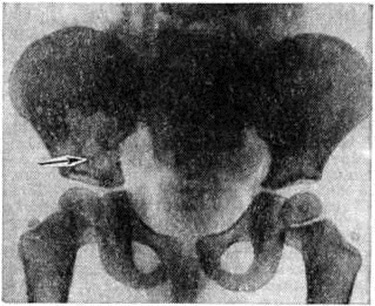

При Л.—С. б. наиболее часто поражаются плоские кости (череп, таз, лопатки). На обзорных рентгенограммах выявляются участки выраженного разрежения с чёткими границами, отдельные очаги достигают размеров 1 — 2 сантиметров Несколько небольших очагов могут сливаться между собой; в этом случае на рентгенограмме обнаруживаются крупные дефекты костной ткани, имеющие волнистые, иногда отчётливые фестончатые контуры (рисунок 2). Деструктивные очаги, разрушая прежде всего губчатое вещество кости, могут нарушать целость и коркового вещества; характерным для Л.—С. б. является отсутствие реакции надкостницы даже в тех случаях, когда при бурном течении процесса оказывается разрушенным и корковое вещество.